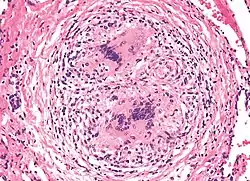

Berylliose, eller kronisk berylliumsygdom (CBD efter eng. Chronic beryllium disease), er en kronisk, allergisk lungerespons og kronisk lungesygdom forårsaget af udsættelse for beryllium og dets forbindelser, en form for berylliumforgiftning. Det er ikke det samme som akut berylliumforgiftning, der er blevet en sjældenhed efter der omkring 1950 blev fastsat grænser for udsættelse på arbejdspladser.[1]